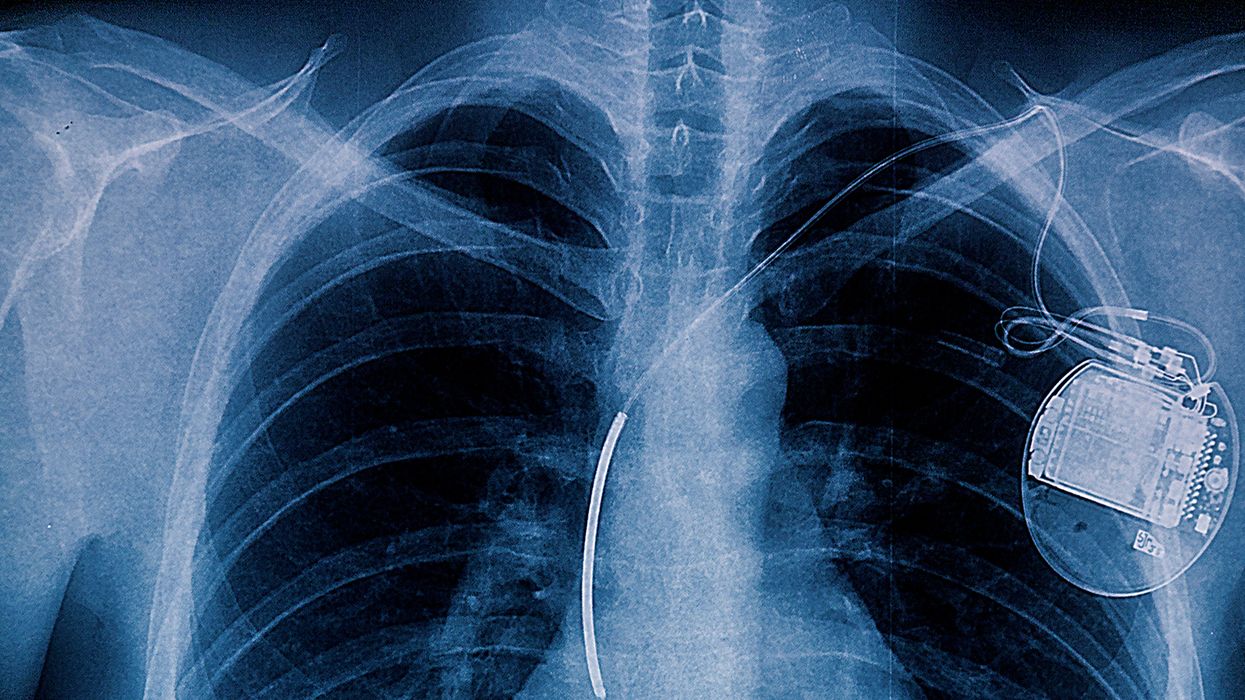

What about pacemakers?

Pacemakers are similar to ICDs but only send low-energy electrical pulses to the heart, while ICDs are more powerful. Pacemakers are not disqualifying and drivers who have them may be medically certified without seeking an exemption.